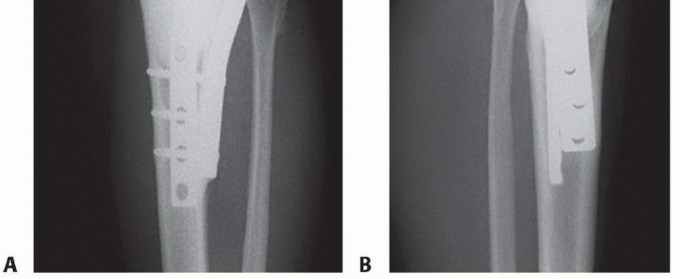

* الجراحة الحافظة للأطراف (Limb Salvage Surgery): تهدف إلى إزالة الورم مع الحفاظ على الطرف المصاب. تتضمن إزالة الجزء المصاب من العظم واستبداله بطعم عظمي، أو مفصل صناعي، أو طرف اصطناعي داخلي (Endoprosthesis). تتطلب مهارة جراحية عالية وتخطيطًا دقيقًا.

* الكشط والعلاج المساعد (Curettage and Adjuvant Therapy): تُستخدم عادة لأورام العظام الحميدة، حيث يتم كشط الورم من داخل العظم، ثم يتم استخدام مواد مساعدة مثل الفينول أو النيتروجين السائل أو الكي الكهربائي لتدمير أي خلايا ورمية متبقية.

مزايا العلاج بالتبريد بالنيتروجين السائل

- حفظ الأطراف: يقلل بشكل كبير من الحاجة إلى الجراحات الواسعة أو البتر.

- طفيف التوغل: يتطلب شقوقًا صغيرة جدًا، مما يقلل من فقدان الدم والألم بعد الجراحة.

- تعافٍ أسرع: فترة تعافٍ أقصر مقارنة بالجراحة التقليدية.

- ألم أقل: عادة ما يكون الألم بعد الإجراء أقل حدة.

- نتائج وظيفية ممتازة: يحافظ على وظيفة الطرف المصاب ومظهره.

- فعالية عالية: فعال في تدمير مجموعة واسعة من أورام العظام الحميدة والخبيثة.

- استهداف دقيق: يسمح بالتحكم الدقيق في منطقة التجميد لحماية الأنسجة السليمة.